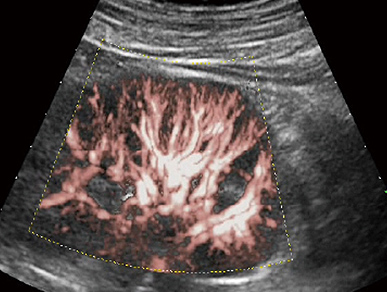

HD CFM

颈动脉高清血流成像

XFlow

肾脏精细血流成像

精细血流成像